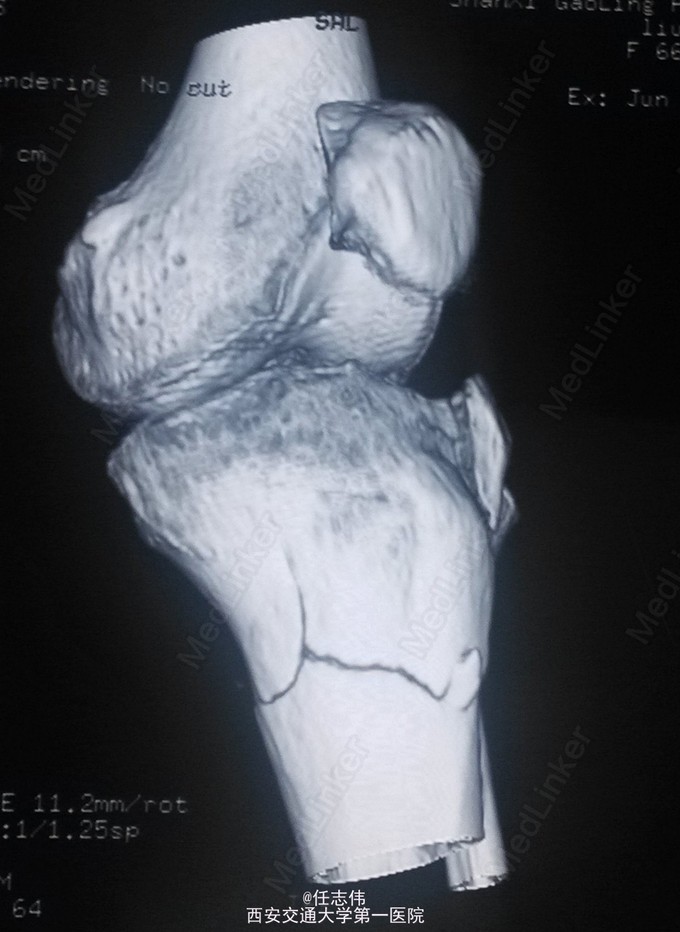

女性,66岁,摔伤致左膝部疼痛活动受限7天 7天前摔伤致左膝部疼痛伴活动受限,在当地医院行跟骨牵引、消肿对症治疗7天,已基本消肿,足部感觉、活动、血供正常。 既往有糖尿病史。

左膝关节周围肿胀,胫骨平台处压痛明显,外侧为著,膝关节活动受限。左足背动脉搏动好,踝及足趾感觉活动正常。

诊断:右胫骨平台骨折 处理:骨折切开复位内固定术。行内外侧入路钢板固定,术中行外侧平台塌陷复位,髂骨植骨内固定。另因考虑有后柱骨折,遂行后外侧切口,支撑钢板固定。术中见患者骨质疏松明显。 术后伤口愈合好,局部仍肿胀明显。

有几个问题想问问: 1.这个是胫骨平台骨折吗?还是胫骨近端骨折伴有平台骨折。 2.手术处理上有什么建议?可以不处理后侧柱吗? 3.大家在复位塌陷平台上有和经验?